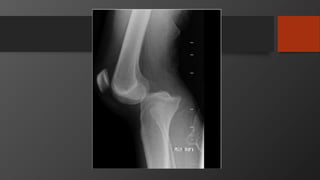

Tibial Plateau Factures

Tibial Plateau Fracture

• Mechanism

• Varus/valgus load with or without axial load

• Like fall from height